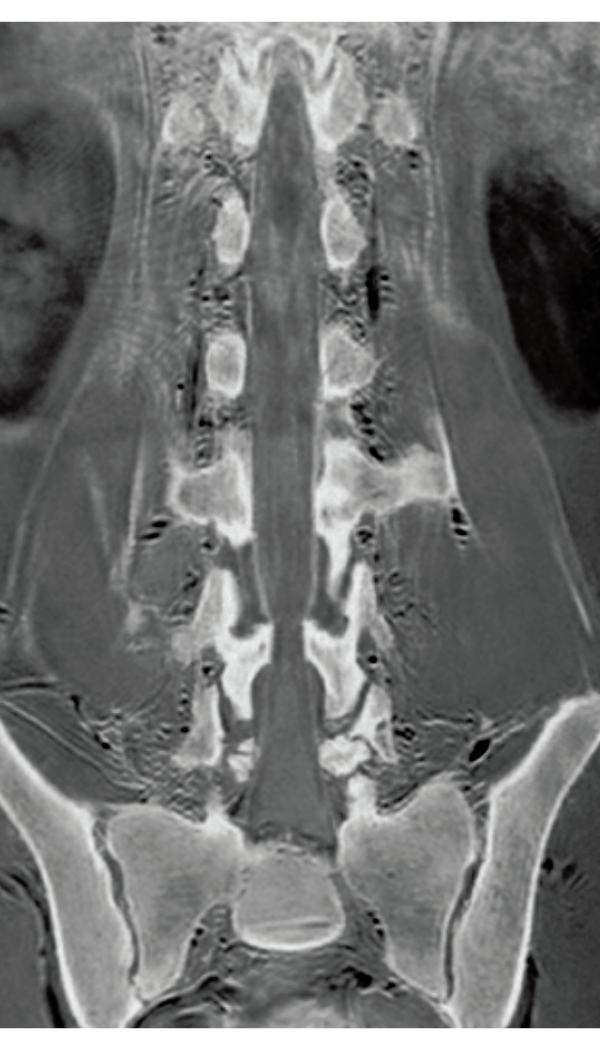

3DisoFSE T2WI

0.75×0.75×1.1(0.55)mm

MPR COR